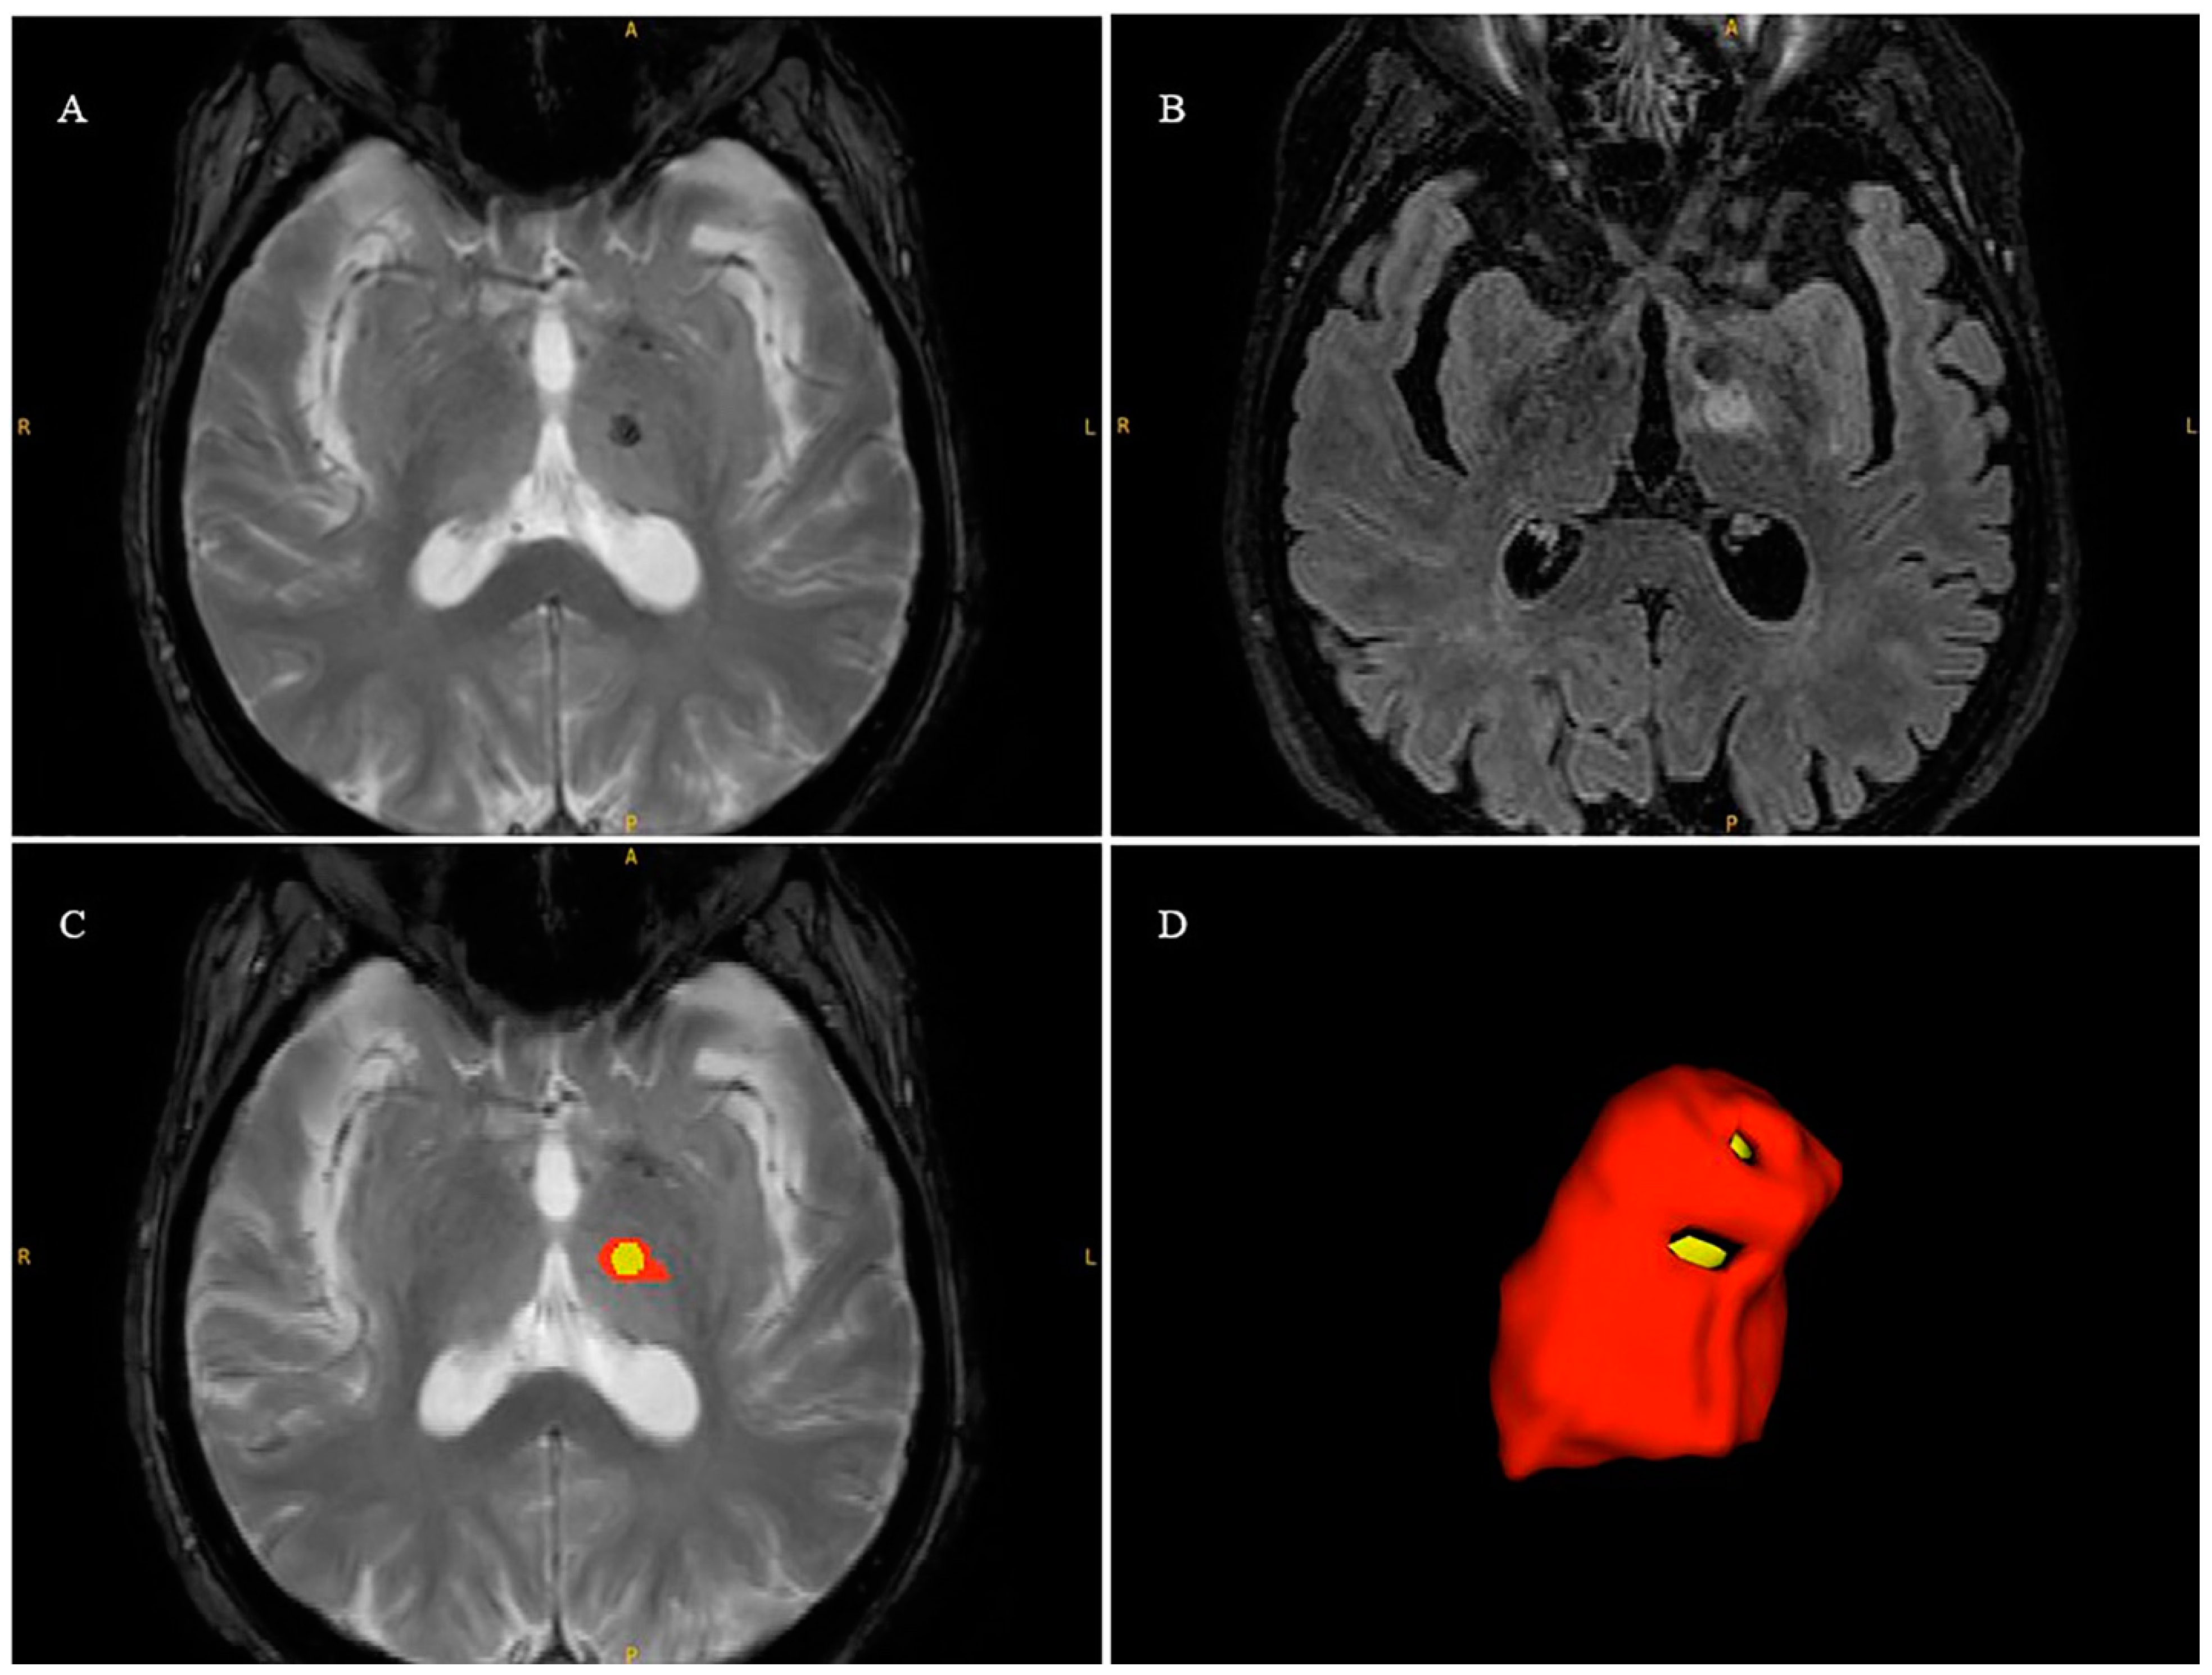

2.7. Lesion Volume Segmentation

| Edema Volume (cm3) | 1607.24 ± 705.5 | 2042.76 ± 895.92 | 0.81 | 0.74 ± 0.13 |

| Necrosis Volume (cm3) | 179.31 ± 135.72 | 153.35 ± 118.56 | 0.88 | 0.70 ± 0.11 |